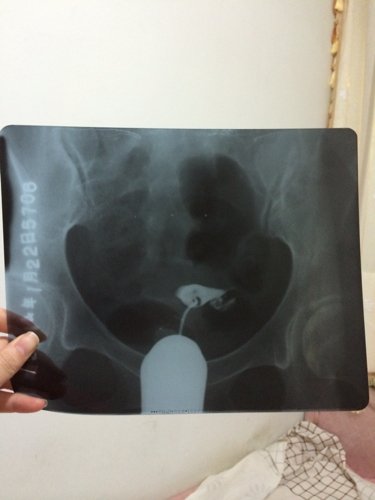

输卵管造影显示结果是左侧输卵管通而极不畅,壶腹部显示扩张,右侧输卵管不完全梗阻,有什么好的治疗方法

输卵管造影显示结果是左侧输卵管通而极不畅,壶腹部显示扩张,右侧输卵管不完全梗阻,有什么好的治疗方法吗?急急!

病情分析: 你好,你的情况不排除左侧输卵管壶腹部有积水的可能。 指导意见: 建议你可以服用中药治疗,同时配合灌肠治疗效果比较好的;也可以做腹腔镜手术治疗的。